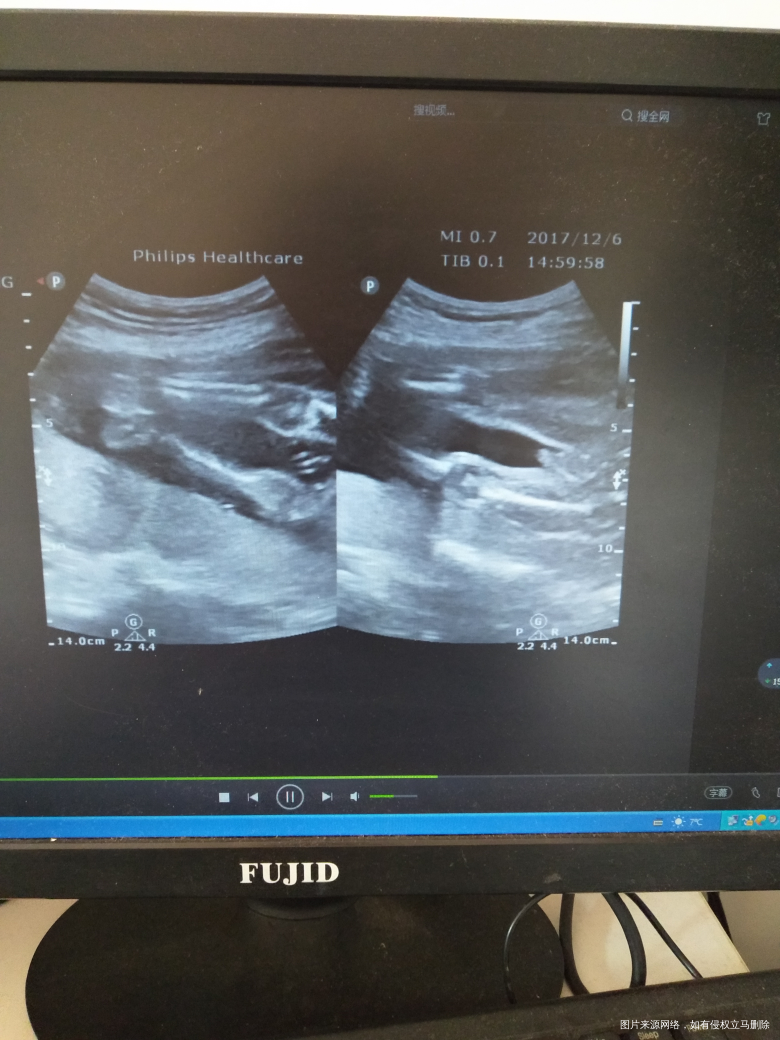

我也不知道,这种问题。该不该问

,但是我真的好想知道自己又看不懂。

这个彩超没法看是男孩还是女孩

若曦 回复 张文娟:为什么呢,这不是最直观的图片吗

你好,这个彩超没法看男孩女孩,只要胎儿健康就好。

你好,做B超的医师在检查的过程中是可以看到的,单纯的图片是看不到的。

你好,一般彩超图片不会让你看出男女,有时候脐带干扰的。